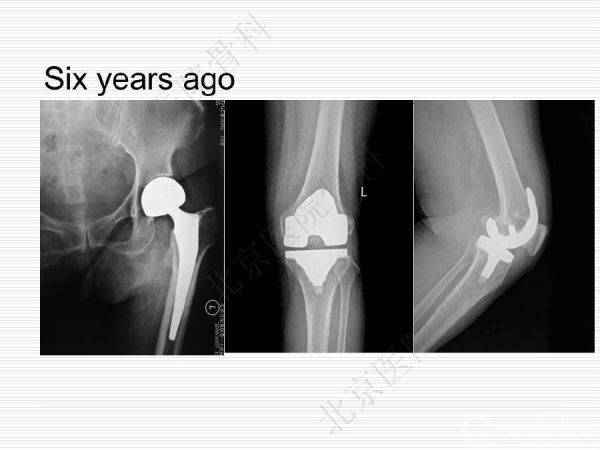

膝关节假体周围骨质疏松骨折1例

骨质疏松性骨折与创伤性骨折不同,是基于全身骨质疏松存在的一个局部骨组织病变,是骨强度下降的体现,也是骨质疏松症的最终结果。骨质疏松骨折是常见病、多发病,严重威胁中老年人身体健康,由此引起的骨质疏松性骨折,除了给患者本人造成极大的痛苦外,也给社会和家庭造成了沉重的经济和生活负担。来自北京医院骨科纪泉教授为我们带来一例经典的《膝关节假体周围骨质疏松骨折》病例,遂抗骨质疏松治疗预防再次骨折,任重而道远!